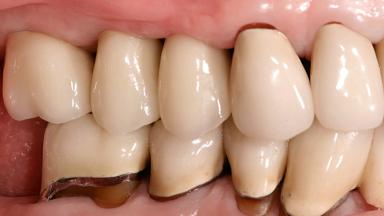

In 2004, an 84-year-old female patient presented at our practice with a hopeless prognosis for her maxillary right first and second premolars. These teeth were supporting a three-unit fixed dental prosthesis and had a cantilevered pontic replacing the first molar. Both teeth had combined endodontic and periodontal lesions, with significant bone loss in the area. The patient also had a large maxillary sinus apical to the first molar site. The patient presented with normal facial form and upon normal smiling, she displayed the affected area. She reported mobility and pain with mastication. The fixed dental prosthesis displayed severe mobility and could be depressed into the alveolar sockets. Exudate was evident around both abutments. There were no significant medical problems reported and the patient reported taking no medications.